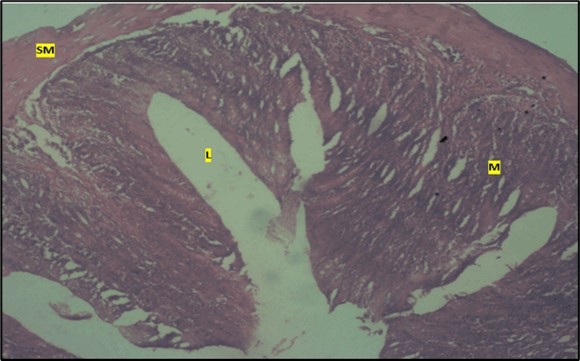

Histological examination of the small intestine result in control animals revealed a normal architecture with the red pulp and white pulp with no pathological observation Figure 2. Administration of Abelmoschus esculentus at low dose shows an increased cellularity with numerous cells in the Mucosa and the villi projecting towards the lumen. Focal metaplasia of mucosal cells alongside villous disruption was also observed (Figure 3). The high dose group showed normal cellular architecture with no villous disruption (Figure 4).

Figure 3.Low dose showing numerous epithelial cells in the mucosa (m) with villi projecting towards the lumen (l). The is focal metaplasia of the mucosal cells with villous disruption. smooth muscle layer appears normal. H & E. X40